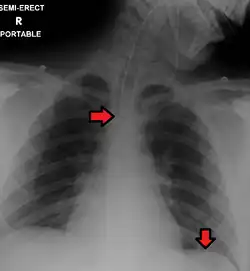

Pleural abnormalities

Fluid in space between the lung and the chest wall is termed a pleural effusion. There needs to be at least 75 mL of pleural fluid in order to blunt the costophrenic angle on the lateral chest radiograph and 200 mL of pleural fluid in order to blunt the costophrenic angle on the posteroanterior chest radiograph. On a lateral decubitus, amounts as small as 50ml of fluid are possible. Pleural effusions typically have a meniscus visible on an erect chest radiograph, but loculated effusions (as occur with an empyema) may have a lenticular shape (the fluid making an obtuse angle with the chest wall).

Pleural thickening may cause blunting of the costophrenic angle, but is distinguished from pleural fluid by the fact that it occurs as a linear shadow ascending vertically and clinging to the ribs.